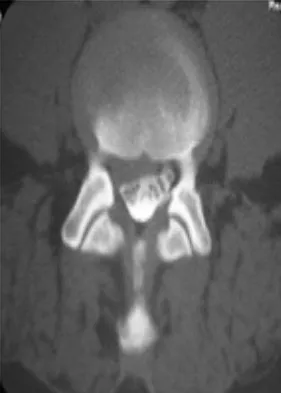

A 37-year-old man has left shoulder pain and weakness. Coronal T1- and axial T2-weighted MRI scans are shown in Figures 17a and 17b. The biopsy specimen is shown in Figure 17c. What is the most likely diagnosis?

Explanation